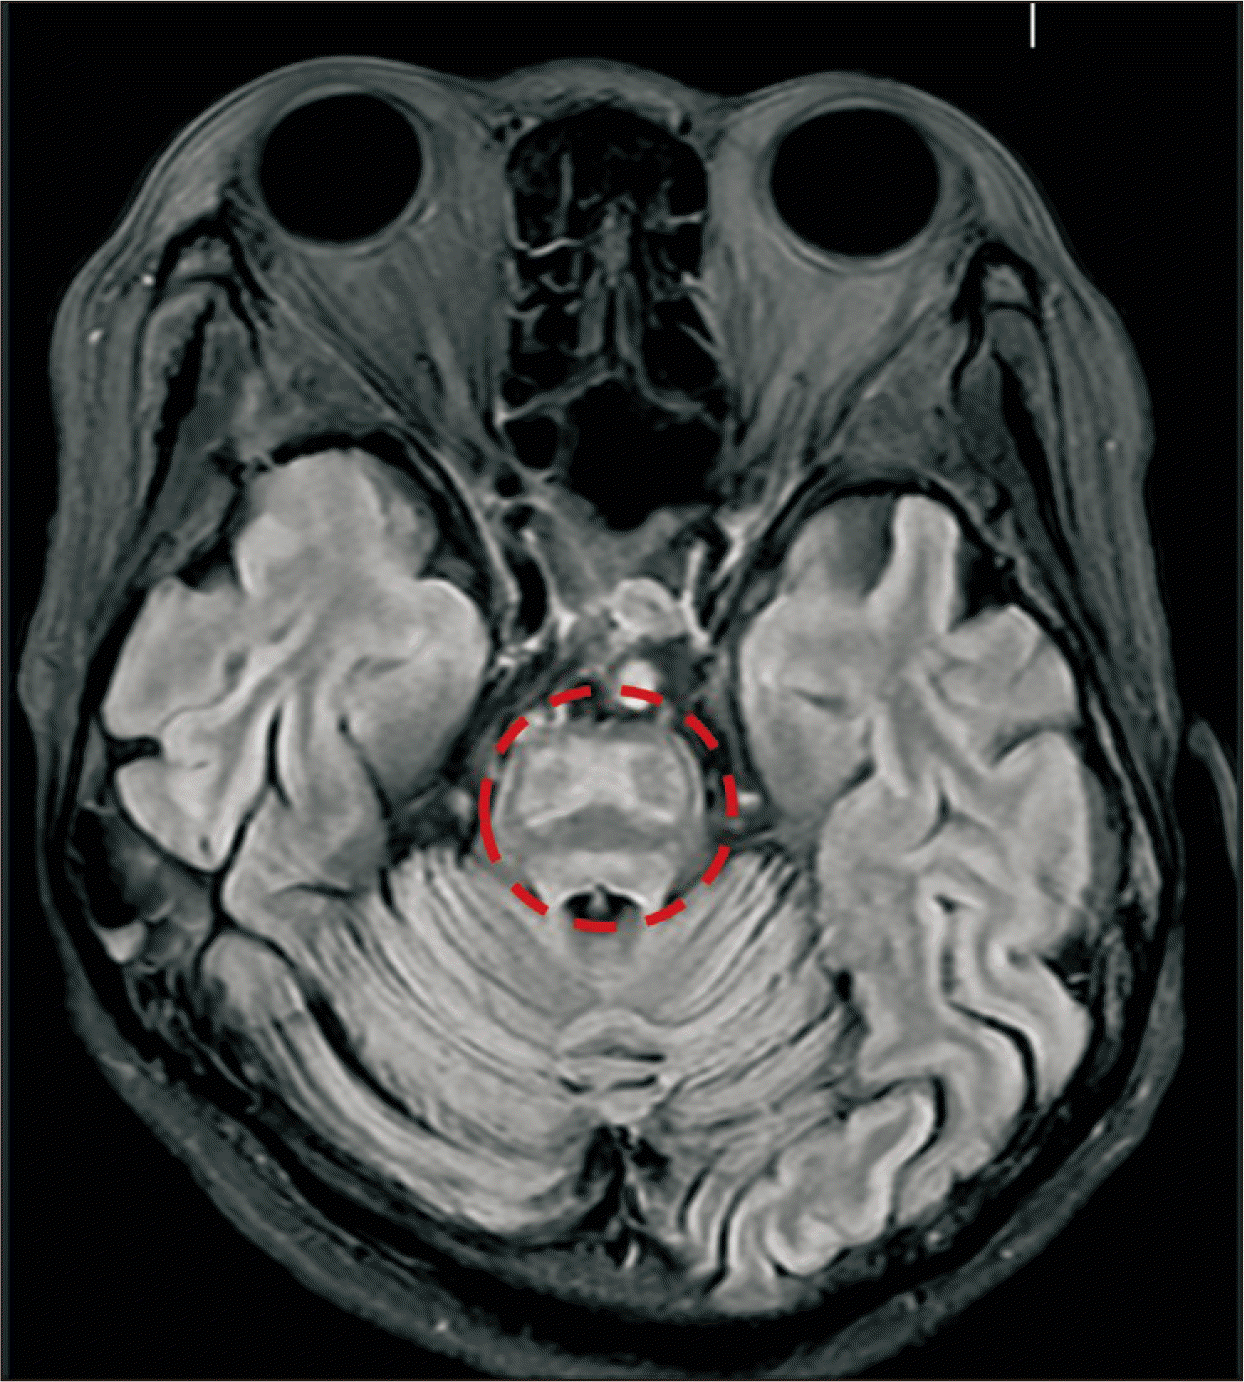

A 43-year-old female patient was diagnosed with acute on chronic liver failure associated with alcoholic liver cirrhosis (Fig. 1) with hyponatremia, and hepatic encephalopathy Grade 3 (Glasgow Coma Scale, GCS 10). Her medical history included partial gastrectomy for obesity in 2002. The patient underwent LDLT. Before transplantation, Rituximab infusion and one session of plasmapheresis were performed due to high titer of cytotoxic antibody. Sodium level was 125 mmol/L, and ammonia level was 231 mmol/L at the time of admission. GCS was 10. Sodium benzoate 4 g/20 mL and lactulose were initiated to decrease ammonia levels in the blood and improve mental status. Ammonia levels started decreasing after sodium benzoate and lactulose treatment, accompanied by slight improvement in mental status. One day before surgery, ammonia levels decreased from 231 mmol/L to 110 mmol/L (Fig. 2), while sodium levels increased from 125 mmol/L to 158 mmol/L. During surgery, a significant blood transfusion was performed, consisting of 8 L blood components - 12 units of red blood cell and 7 units of fresh frozen plasma. Sodium levels during surgery ranged from 150–153. Reperfusion caused severe bradycardia (heart rate 20), corrected by epinephrine 100 mcg IV. Post-LT, the patient was transferred to the intensive care unit. In postoperative period, liver doppler and liver function tests were normal, and postoperative liver computed tomography (CT) scan at postoperative 5th day showed normal findings (Fig. 3). Despite this, the patient remained unresponsive to commands and exhibited a tendency to sleep. Post-surgery ammonia levels decreased to 110 with a declining trend and normalized on post-operative day (POD)#2–3 (Fig. 2). However, the patient’s mental status deteriorated, with GCS score decreasing from 10 to 6. Sodium levels initially increased to 160 but normalized after POD#5. Electroencephalogram showed delta slowing, and Brain CT scan revealed no significant abnormalities. Magnetic resonance imaging (MRI)+diffusion-weighted imaging revealed CPM (Fig. 4). Conservative treatment was initiated, maintaining tacrolimus levels below 5 to prevent CPM progression, and vitamin B (thiamine) supplementation was provided. Levodopa was administered, resulting in improvement in mental status and GCS from 6 to 12 after POD#19.

CPM is defined as symmetrical demyelination of the central area of the pons. Based on autopsy results, the incidence of CPM after LT ascends to 17% and is associated with a high mortality rate (50% or higher) [3]. Liver transplant recipients have a high prevalence of predisposing factors for CPM, such as electrolyte imbalances, liver disease, diabetes mellitus, malnutrition, chronic hyponatremia, hypoxia, and certain medications (barbiturates, diuretics, cytostatics, sodium benzoate, lactulose). Changes in serum sodium due to large volume shifts during transplantation have been associated with CPM [2,4]. A chronic hypo-osmolar state (Na<120 mmol/L for more than 2 days) and its rapid correction (but not an acute and brief episode of hyponatremia) are common attributable factors for the development of CPM [1,2]. After 1979, the US Food and Drug Administration approved sodium benzoate to treat hepatic encephalopathy with hyperammonemia [5], but as with lactulose, the use of sodium benzoate may raise serum sodium levels and increase the chance of CPM [6,7], as in our patient’s case. In most cases developing CPM is based on postoperative and intraoperative processes but we described that there is also cases when perioperative care such as injection sodium benzoate and lactulose for decrease ammonia level and improve patient mental status can induced and increase CPM risk after LT. The clinical appearance of symptoms occurs from 2–7 days after the injury, depending on the brain areas affected. It can debut as progressive confusion, neuropsychiatric disorders, seizures, dysphagia and dysarthria, spastic quadriplegia, locked-in syndrome, or coma [4]. In patients who present with these signs and symptoms following liver transplant, suspicion of CPM should be raised, especially in high-risk patients, even in the absence of electrolyte imbalance, because radiological MRI imaging changes, which more accurately confirm the diagnosis, can take up to 20 days to appear [7].